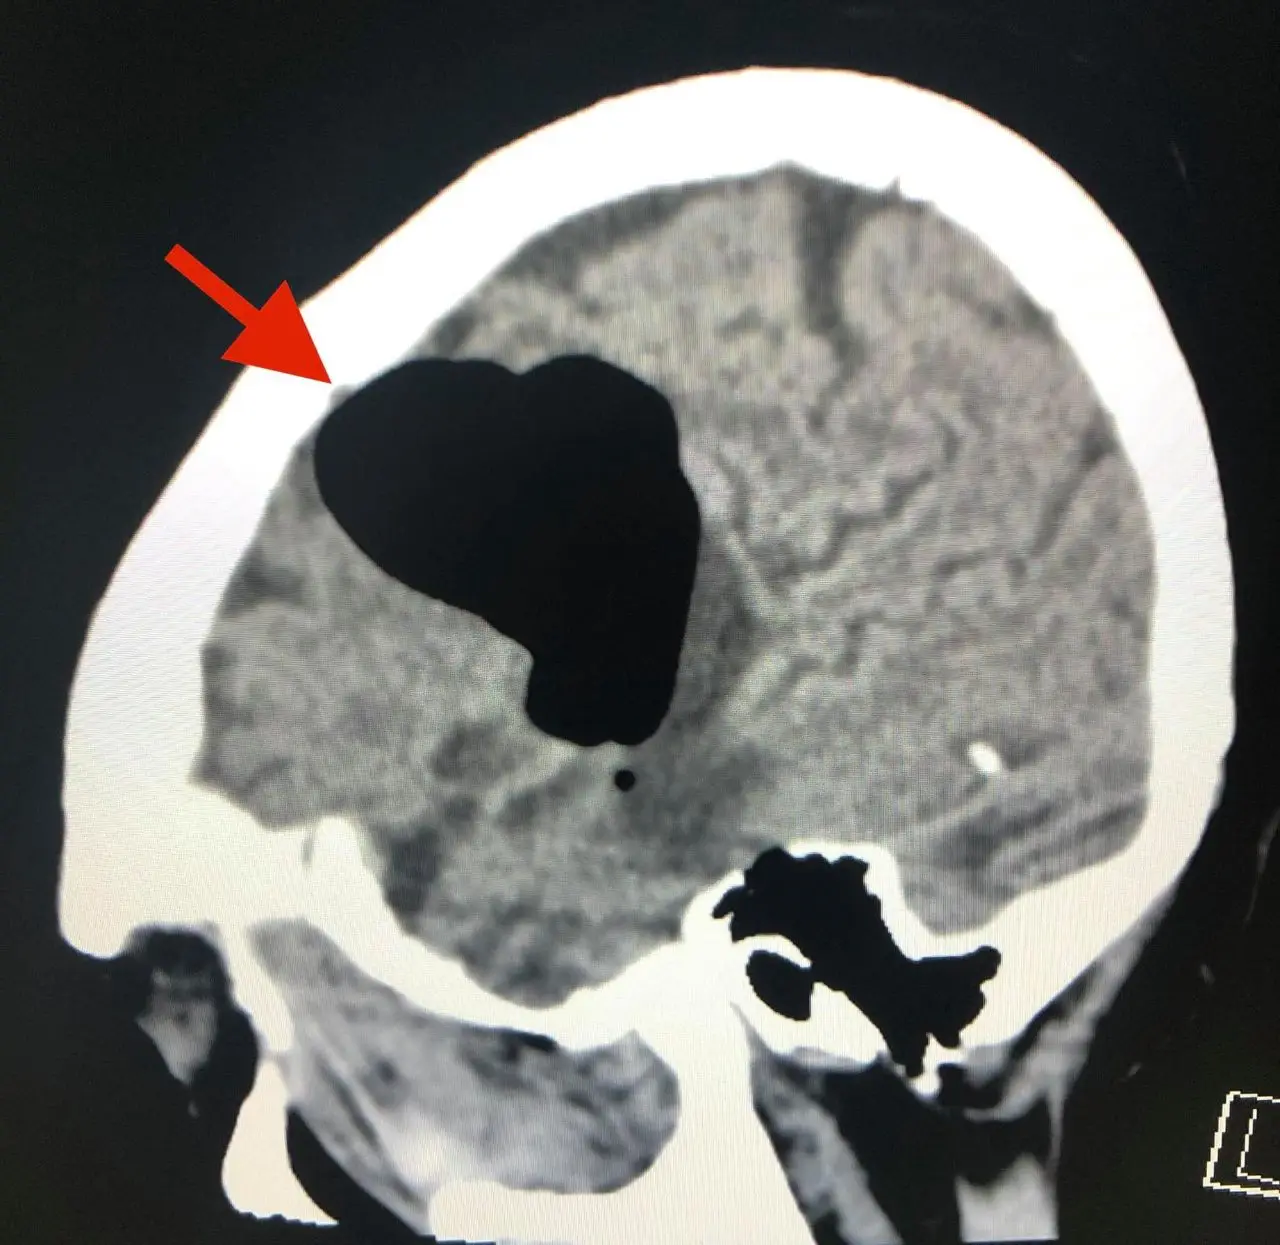

วันที่ 14 พฤษภาคม 2563 ผู้ป่วยกลับมารพ.อีกครั้งหลังจากจามแล้วเอามือปิดปากปิดจมูกเพราะไม่อยากให้มีเสียงดัง หลังทำมีอาการพูดไม่ชัด หน้าข้างขวาเบี้ยว หูข้างซ้ายอื้อ มีเสียงดัง ทำคอมพิวเตอร์สมองพบลม (air pocket) ในเนื้อสมองข้างซ้ายขนาด 5.1 × 4.1 × 2.8 เซนติเมตร (ดูรูป) ตำแหน่งเดิมเหมือนเมื่อ 3 ปี 5 เดือนก่อน แต่ปริมาตรของลมในเนื้อสมองครั้งนี้น้อยกว่า ผู้ป่วยนอนในโรงพยาบาล 4 วัน อาการดีขึ้นช้าๆ กลับบ้านได้